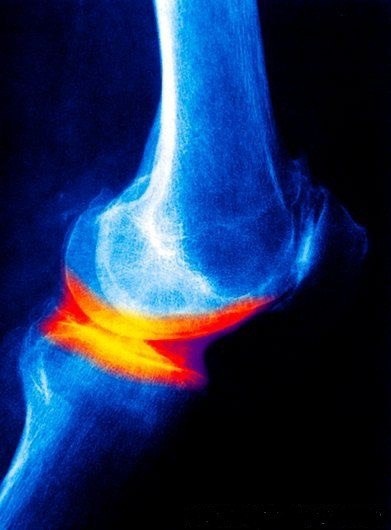

Хотите остеоартроз? Тогда следуйте этим советам! 😁 ✅ Носите всё на своих плечах. И не только моральные бремена! По возможности увеличивайте свой вес – это отлично ускорит износ суставов. Чем тяжелее, тем лучше! ✅ Превратите диван в лучшего друга. Упражнения? - Подолгу сидите перед телевизором или компьютером. Активность переоценена, так что минимизируйте движение, чтобы ваши суставы заржавели как старый велосипед. ✅ Ешьте что угодно, кроме здоровой пищи. Фастфуд, сладости и газировка — ваши лучшие друзья. Забудьте о скучных омега-3 и кальции. Организму наверняка нужно больше сахара и транс-жиров! ✅ Берегитесь спортивного оборудования, как огня. Зачем поддерживать мышцы в тонусе? Слабые мышцы и нестабильные суставы — это то, что нужно для непредсказуемой и интересной жизни. ✅ Не обращайте внимания на боли в суставах. Вероятно, они просто пытаются вас о чём-то предупредить. Но знания — это сила, а вам этого совсем не нужно! Следуйте этим советам, и ваши суставы обязательно